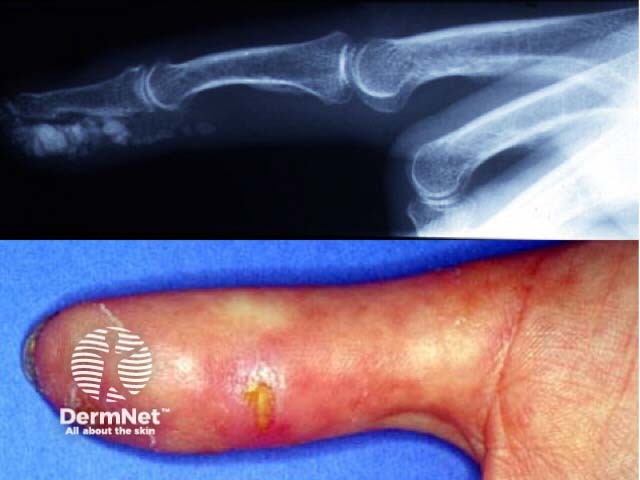

The CREST variant (Calcinosis, Raynaud's, oEsophageal, Sclerodactyly, Telangiectasia) may have less severe systemic manifestations.

Severe digital resorption

CRST syndrome

Calcinosis cutis